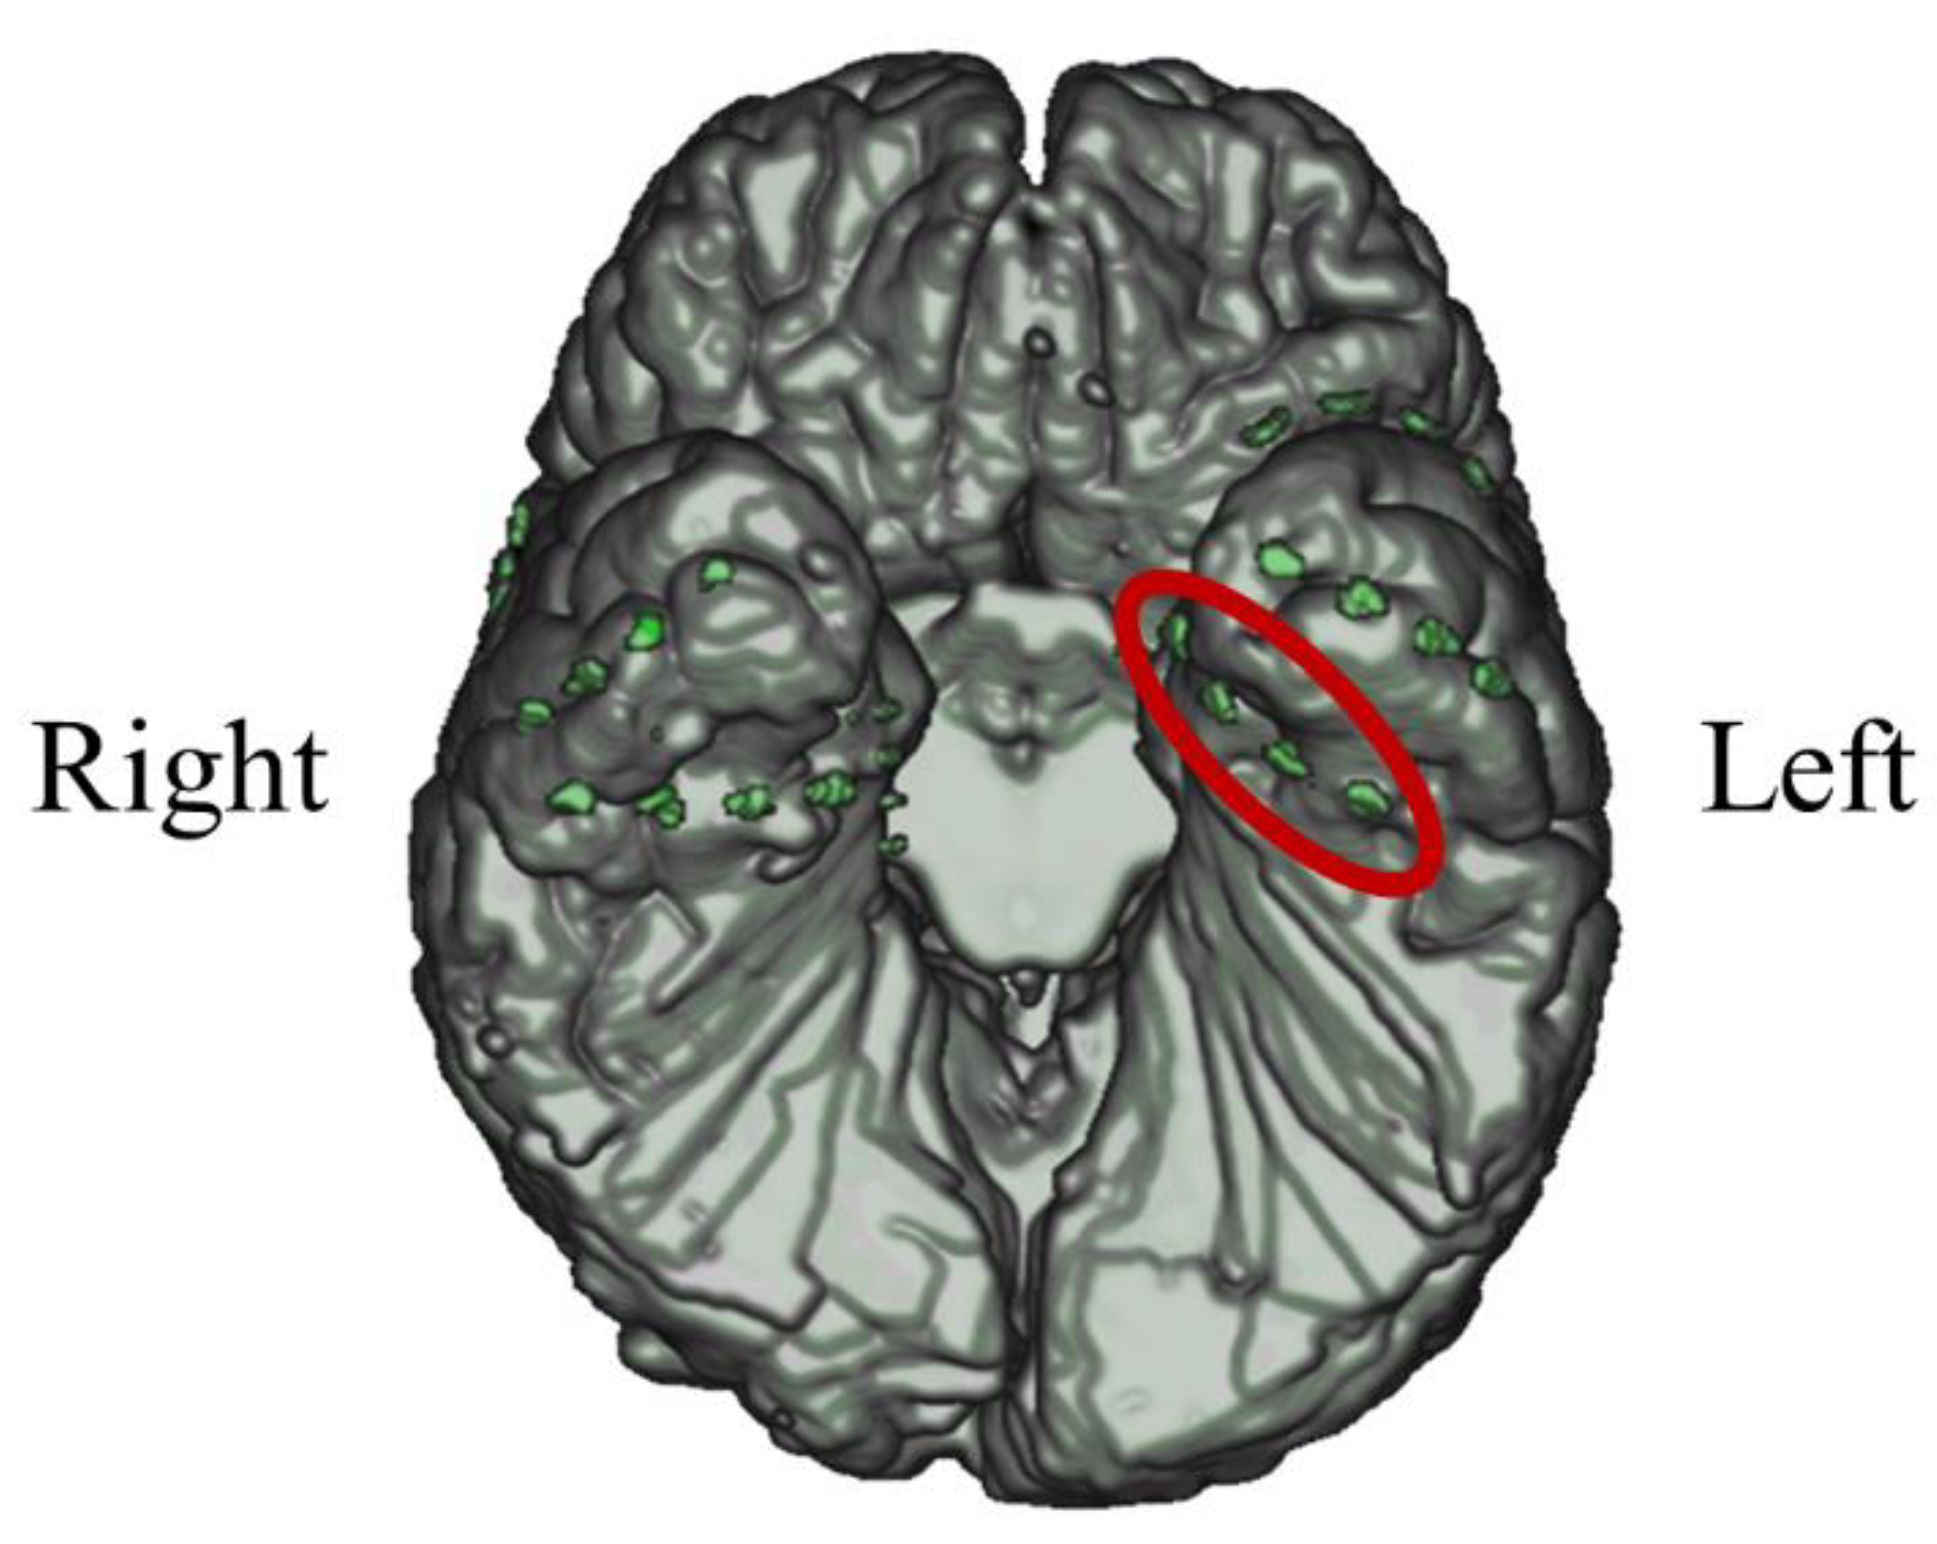

3.2.1. Intracranial Electrodes Used for Memory NF (P02)

3.3.1. Intracranial Electrodes Used for Memory NF (P03)